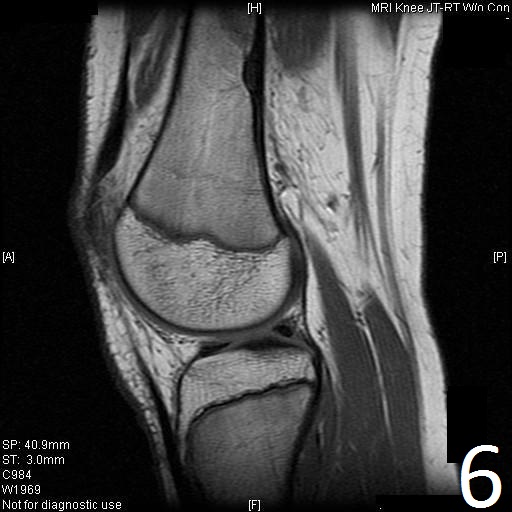

MRI

• Low- signal on T1 (Fig. 8)

• Variable heterogeneneous signal on T2 (Fig. 9).

• Possible extensive hypercellular fibrous tissue and hemosiderin seen on T2

Fig. 6-9: Sagittal T1 (Fig. 6) and T2 (Fig. 7) MRI of the knee demonstrates a fibrous cortical defect. Axial T1W (Fig. 8) and T2W (Fig. 9) show a heterogeneous lesion on distal femur, compatible with nonossifying fibroma.